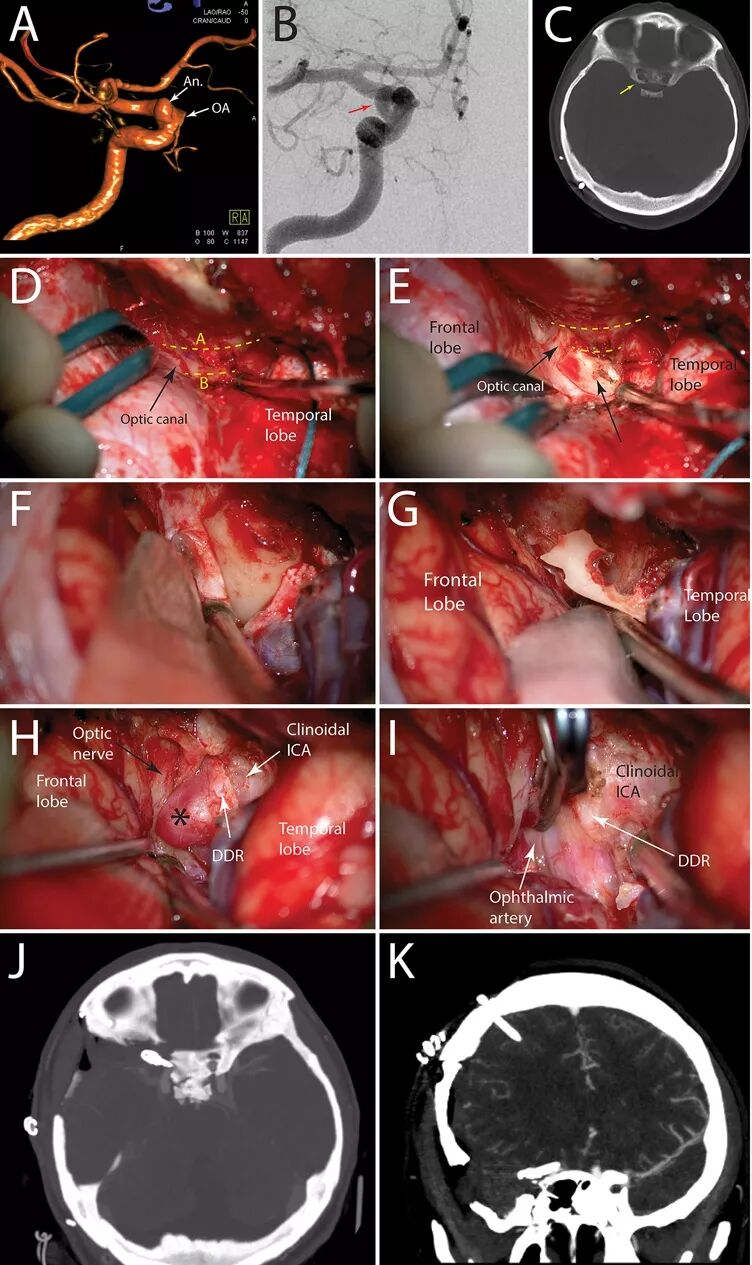

图4. 1例女性,41岁,右侧颈内动脉床突段动脉瘤患者。A、B.DSA示右颈内动脉床突段动脉瘤;C. CT显示右侧颈动脉床突孔(黄色箭头);D.右侧翼点入路,切开眶脑膜缘,分离中颅窝底硬脑膜和海绵窦外侧壁,显露OC(黑色箭头);E.硬膜外磨除部分前床突,其余留在硬膜内磨除;H.切开硬脑膜,进入硬膜下分离外侧裂,牵开额、颞叶,打开颈动脉池,切开并剥离覆盖前床突的硬脑膜,磨除并取出残余的前床突,暴露动脉瘤(星号所指);I.切开远环(白色箭头),确认眼动脉并予以保护,夹闭动脉瘤。术后复查CTA提示,动脉瘤完全夹闭,术后患者恢复良好,无神经功能缺损。